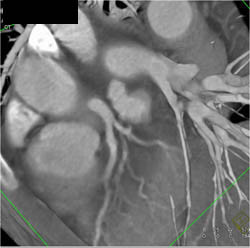

Takayasu's Arteritis